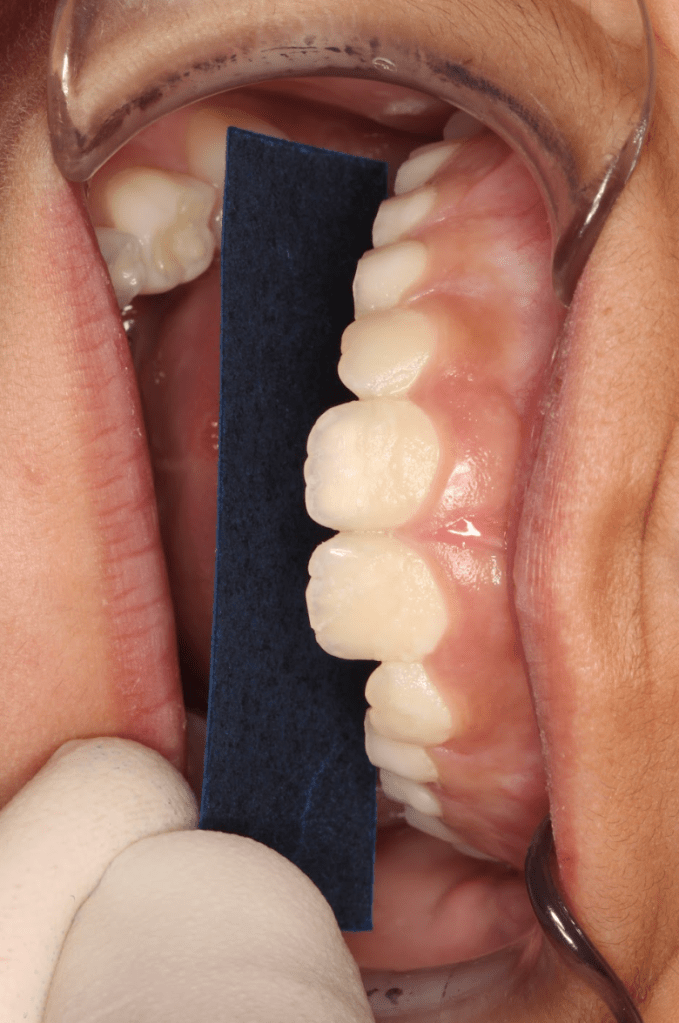

Reconstrucción preendodóntica

Gingivectomía +reco preendo +reconstrucción

Molar superior

Reco palatina

Reco pared vesticular

Reco pre-endo gingivectomái, pared yuxtaosea

Reco pre-endo, molar inferior

Reco preendo + 4 conductos molar superior

Reco preendo + gingivectomía

Reco preendo, 2o Molar superior

Reconstrucción debajo de puente